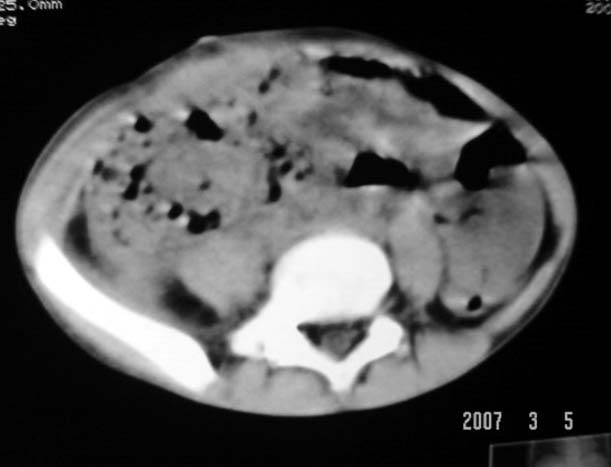

以下是引用dyqct在2007-3-5 10:28:00的发言:[br]右髂窝肿块。[br][br][br][br]